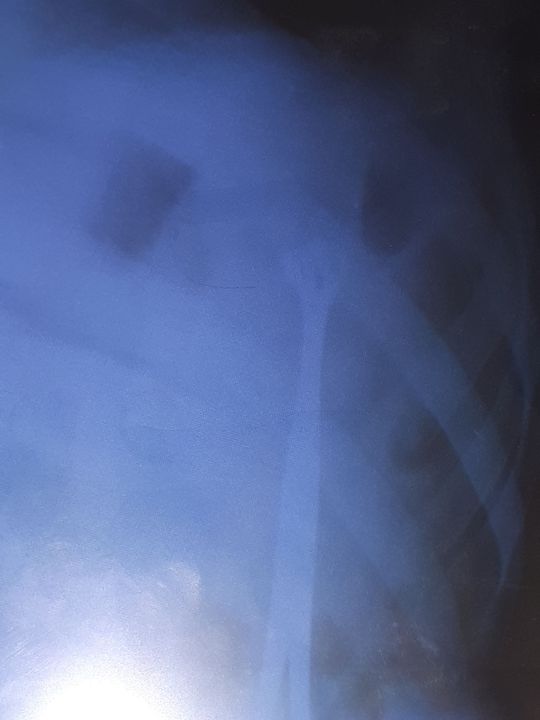

What is this?

A young boy with abdominal shell injuries 2month ago.

Shock

Painful

Hypovlemic